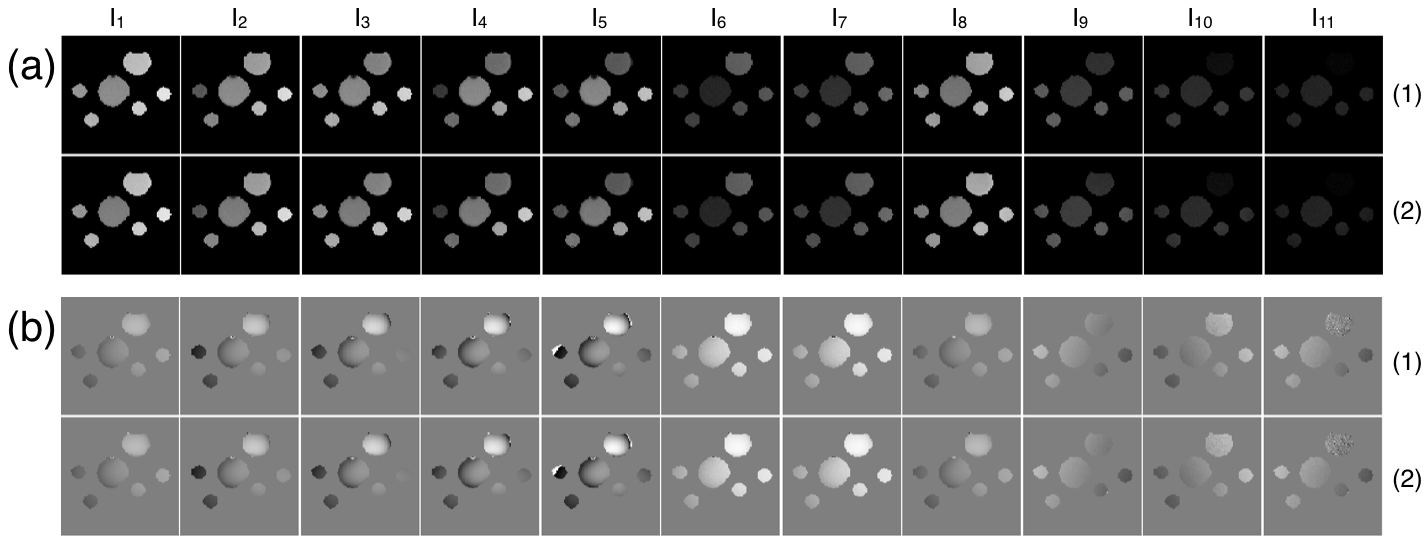

Figure 3 shows the axial slice images generated by the multiMap sequence. Figure 3 (a) and (b) show the magnitude and phase images, respectively. The top/bottom rows of each sub-image show the acquisitions of the first/second segments, respectively for a multiMap scan with a repetition time of ms and a saturation recovery time of ms. The total scan time for this image was minutes and seconds.